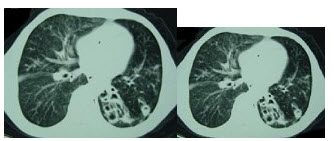

9、单项选择题

患者,男,56岁,无明显诱因突然咯血入院,作CT检查如图,病变的肺叶(段)定位应为()

A.右肺下叶内基底段

B.右肺上叶尖、后段

C.右肺中叶

D.右肺上叶前段

E.右肺下叶后基底段

48、单项选择题

女,19岁,低热,盗汗,乏力,咳嗽1月余,CT检查如图,最可能的诊断是()

A.间质性肺炎

B.弥漫型肺癌

C.粟粒型肺结核

D.矽肺

E.大叶性肺炎